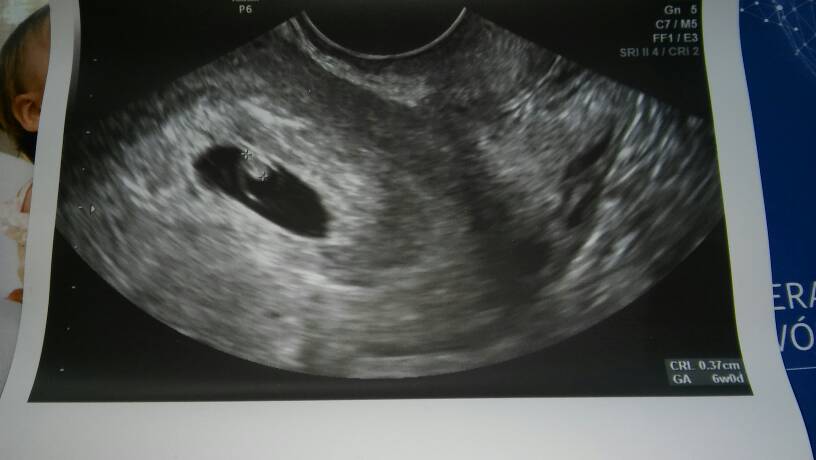

A który to tydzień u ciebie?Zobacz załącznik 811709

Mowil ze musialam mieć opozniona owulacje nawet o 3dni i dlatego tak sie dzieje. I powiedzial tez ze jak uslyszymy za tydzien serduszko to on sam bedzie spokojniejszy

Jest to jak najbardziej prawdopodobne,że owu była późniejZobacz załącznik 811709